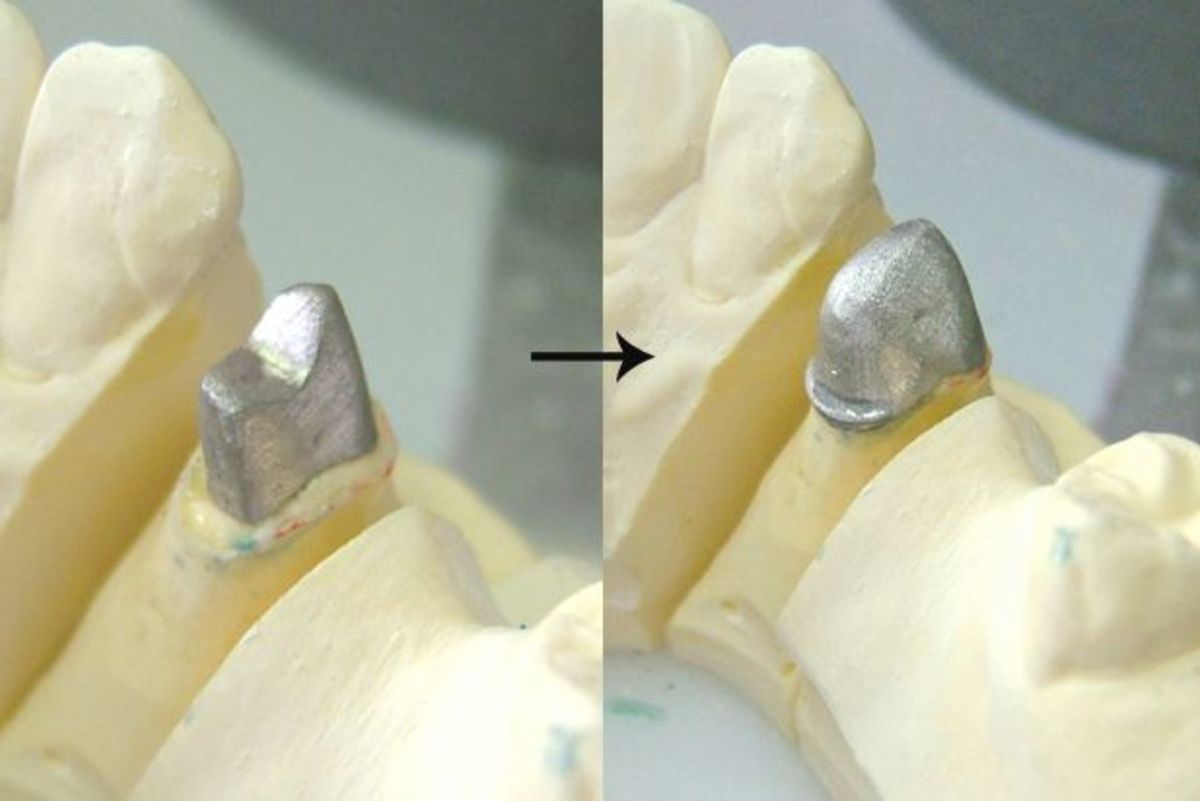

Культя зуба это

Культя зуба это 106 фото